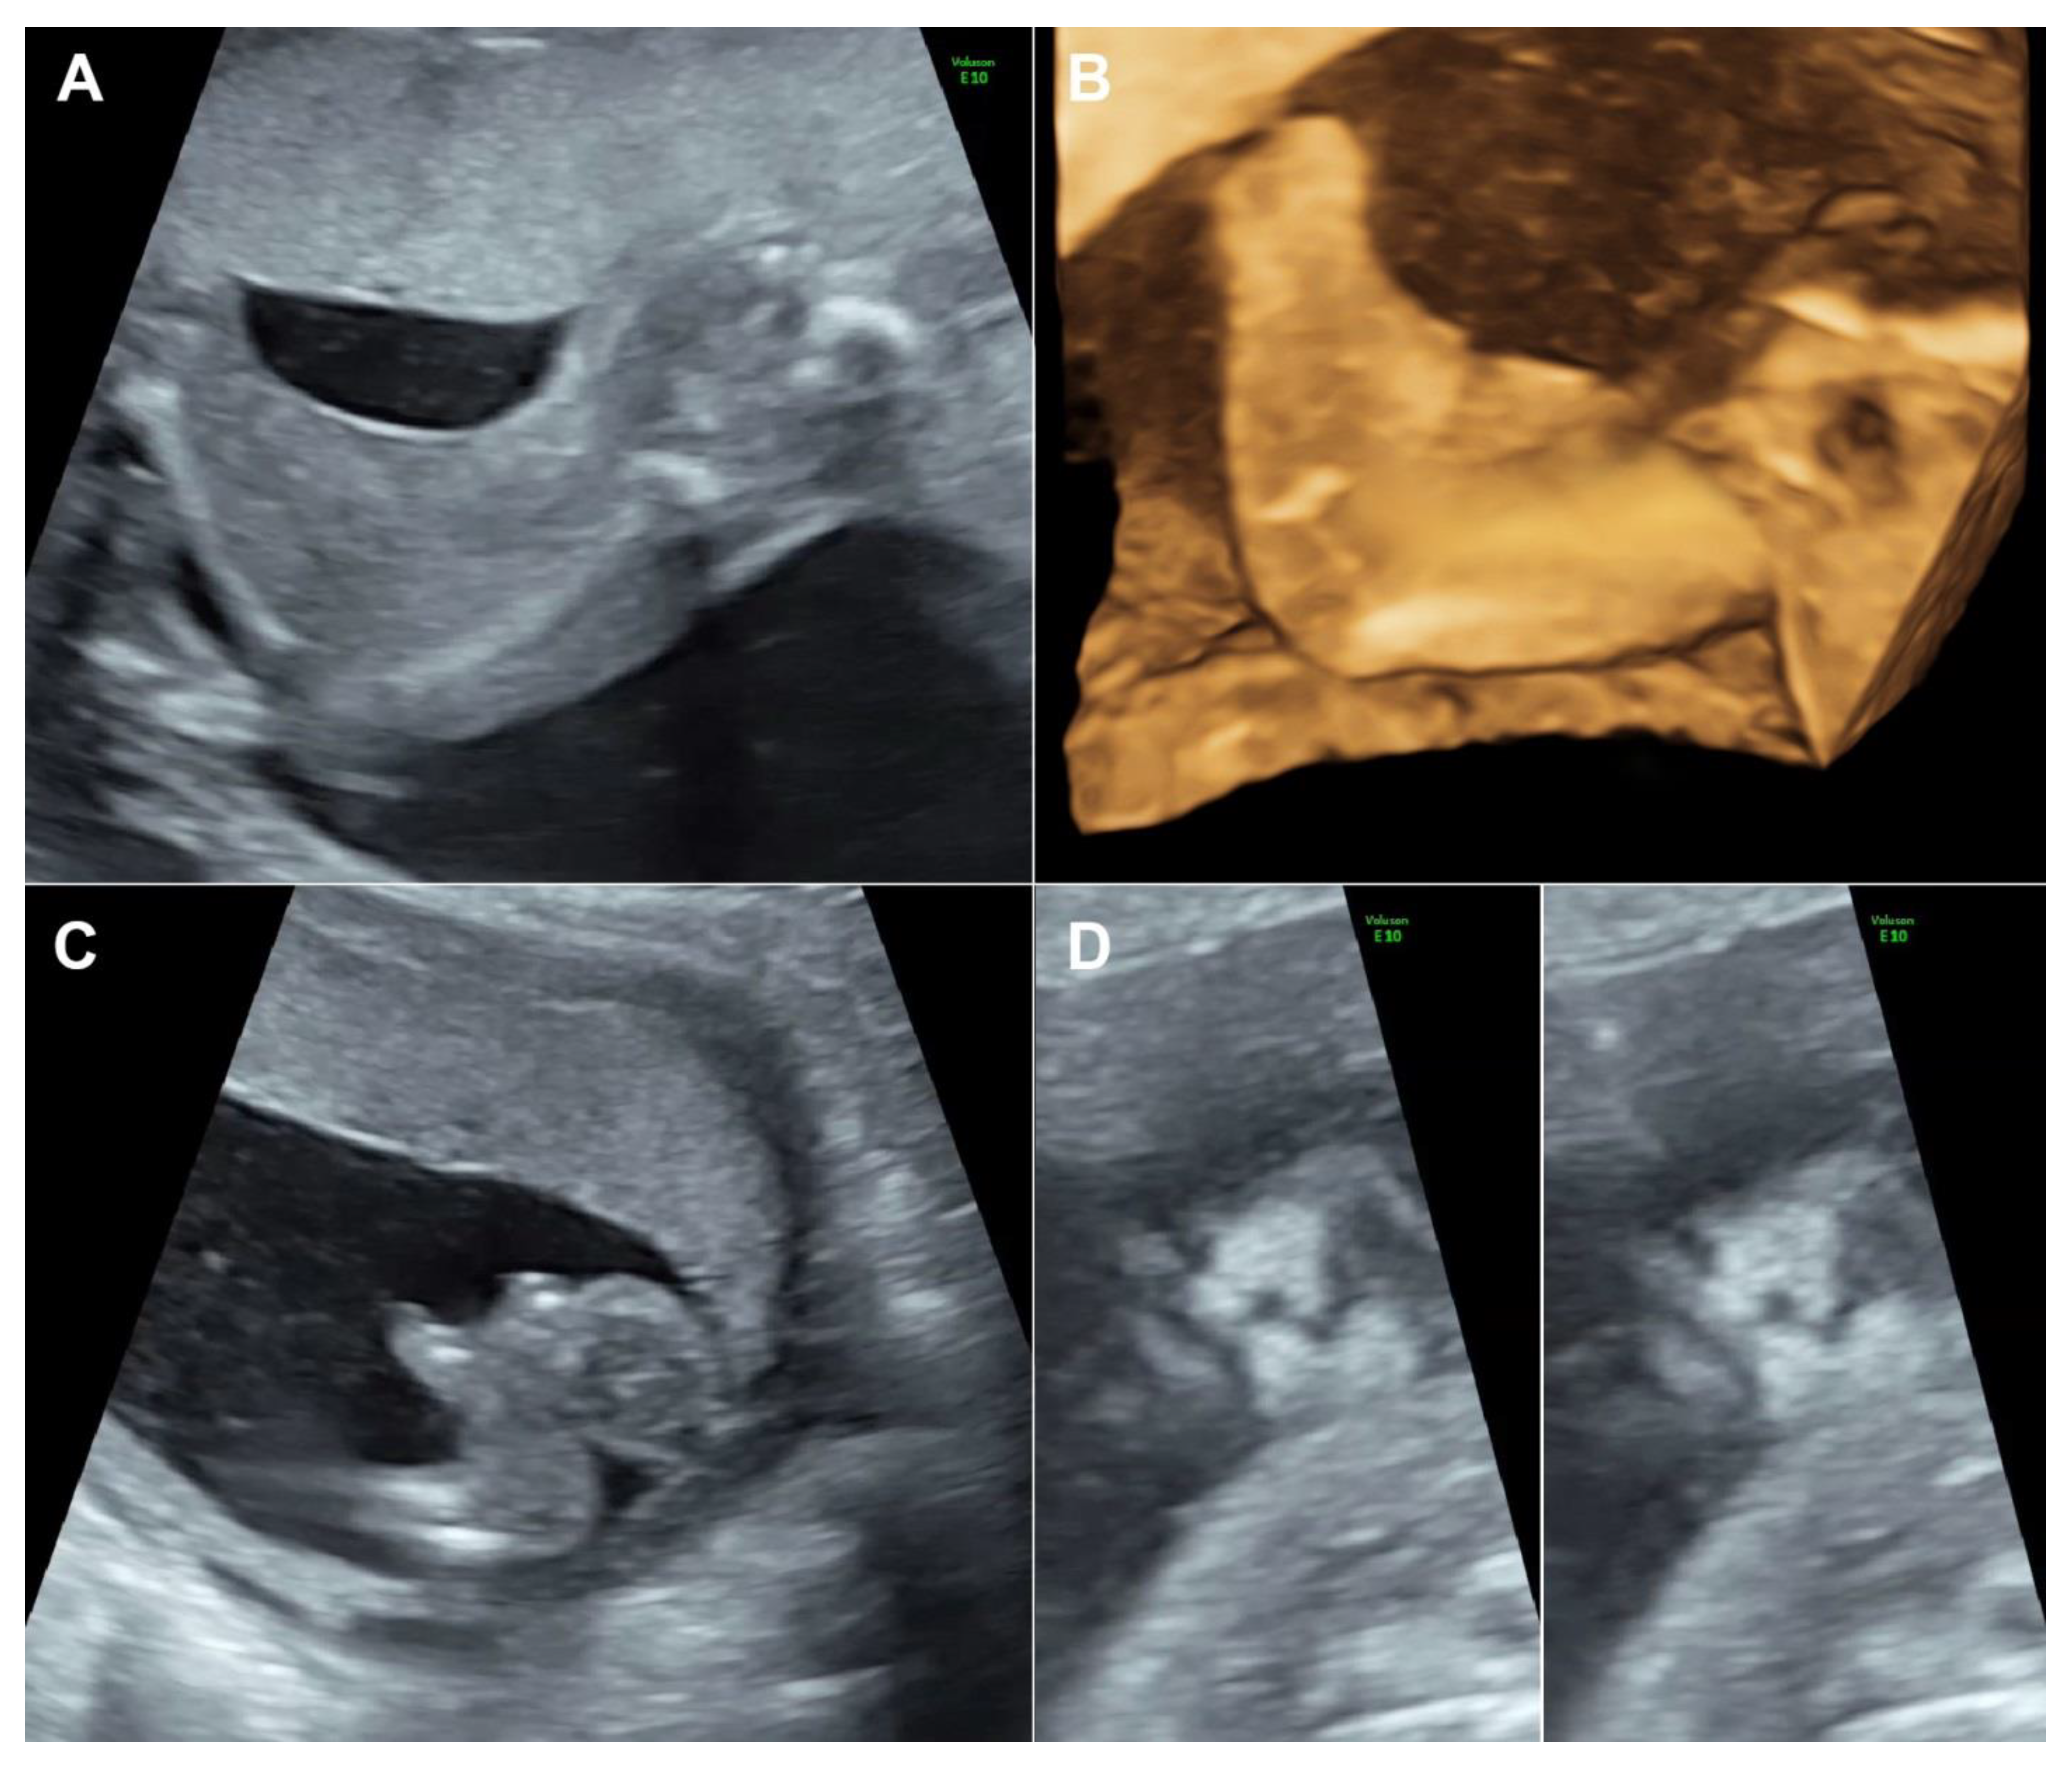

A 30-year-old pregnant woman, G3 P1011, presented for antenatal care and fetal anomaly screening at 20 weeks of gestation. She had no serious underlying medical disease, except left traumatic optic neuropathy. Also, her familial history was unremarkable. The first pregnancy ended up with miscarriage at 8 weeks of gestation. The second pregnancy gave birth to a healthy term female newborn, weighing 3550 g. The current pregnancy course was uneventful. Ultrasound examination for fetal anomaly screening at 20 week of gestation showed a single viable fetus with abnormalities as follows (Figure 1): bilateral popliteal pterygia extending from posterior aspect of the thighs to the heels with restriction in extension of both knees (no more than 90°), bilateral talipes equinovarus, syndactyly and ectrodactyly of the toes, ambiguous genitalia (penis-like phallus with poorly developed scrotum and suspected of hypospadias) and suspicious of cleft lips (variant). Biometry was consistent with gestational age (using Voluson E10 machine equipped with transabdominal 2- to 4-MHz curvilinear transducers; GE Healthcare Ultrasound, Milwaukee, WI, USA). The placenta was normal and amniotic fluid volume was normal. Both upper limbs were structurally normal and had normal movement. No other structural anomaly was identified. Fetal cord blood which was obtained by cordocentesis and parental blood samples were sent for trio whole-exome sequencing. Because of the severe abnormalities of both lower extremities and genital structures, the couple requested to have the pregnancy terminated. Therapeutic abortion was performed using transvaginal misoprostol. A male fetus with ambiguous genitalia was aborted at the 20 weeks of gestation, weighing 420 g. Postnatal findings confirmed the prenatal sonographic features (bilateral popliteal webs extending from posterior aspect of the upper thighs to the heels with bilateral talipes equinovarus, syndactyly and ectrodactyly of the toes, and ambiguous genitalia), as presented in Figure 2. The placenta was grossly normal. Fetal karyotype was 46, XY. The molecular genetic analysis by whole-exome sequencing was subsequently performed. All exon regions of all human genes were captured by xGen Exome Research Panel v2 (Integrated DNA Technologies, Coralville, IA, USA). The captured regions of the genome were sequenced with Novaseq 6000 (Illumina, San Diego, CA, USA). The raw genome sequencing data analysis, including alignment to the GRCh37/hg19 human reference genome, variant calling and annotation, was conducted with open-source bioinformatics tools and in-house software (3 billion Inc. Seoul, Seoul, Korea). The result revealed a heterozygous pathogenic variant in IRF6 (NM_0061474; c.250C > T; p.Arg84Cys) in the fetus, consistent with molecular diagnosis of Popliteal Pterygium Syndrome type 1 (MIM #119500). This condition is inherited by autosomal dominant manner. However, trio analysis in this family proves that the pathogenic variant in the affected case occurred de novo. Therefore, the recurrent risk in the next pregnancy is less than 1%. This information was provided to the couples.

Figure 1.

(A) Webbing from the posterior aspect of the thigh extending to the heels; (B) 3D-US reconstruction of the lower limb shows popliteal webbing; (C) Club foot shows ectrodactyly; (D) Coronal view of the fetal face shows bilateral grooves of the upper lip (left: superficial plane; right: deeper plane).

The case presented here emphasizes on careful delineation of anatomical survey. Abnormal posture of the lower limbs including clubfeet (equinovarus), restriction of lower limb movement was the first clue, warranting detailed ultrasound. Actually, the well-defined popliteal pterygia can be simply missed, if not exactly midsagittal scans of the lower limbs. It is noteworthy that cross-sectional scans, oblique scans or coronal scans along the long axis view of the lower limbs cannot clearly demonstrate the popliteal webbing. The examiner must carefully identify the true midsagittal scans to clearly visualize the popliteal webbing as presented in Figure 1 and Video 1. In cases of high suspicion, 3D-ultrasound can be helpful in reconstruction to demonstrate the webbing (Figure 2). On literature review, popliteal webbing is very rarely demonstrated clearly with prenatal ultrasound. Nevertheless, since the sonographic images of extremities can be visualized in early gestation, it is, theoretically, possible that the popliteal webbing can be detected earlier in late first trimester or early second trimester. However, the diagnosis in our case, unfortunately, was detected at 20 weeks of gestation, relatively late, since we routinely perform anomaly screening at mid-pregnancy, while first trimester screening is only optional, not routine.